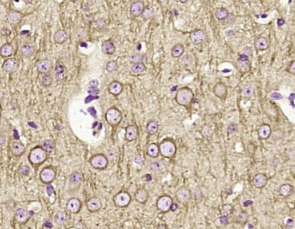

多聚甲醛固定,石蜡包埋(小鼠脑);用柠檬酸钠缓冲液(pH6.0)煮沸15min后获得抗原;用3%过氧化氢阻断内源过氧化物酶20分钟;阻断缓冲液(正常山羊血清)37℃30min;用β-微管蛋白单克隆抗体进行抗体孵育未结合的单克隆抗体在1:400在4°C下过夜,然后根据SP试剂盒(小鼠)说明和DAB染色进行操作。